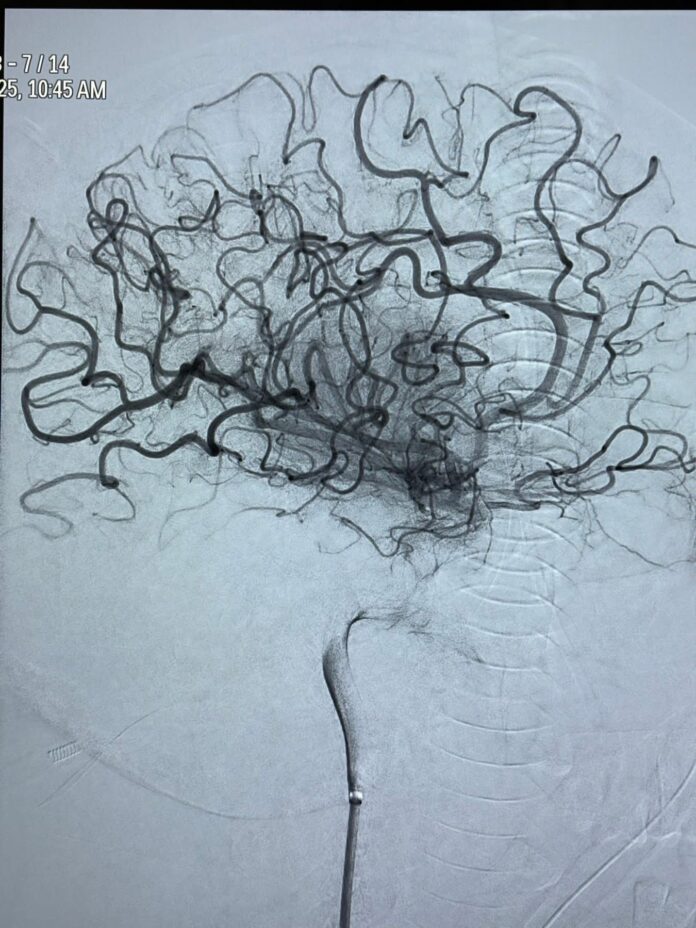

“Procedura de trombaspirație (îndepărtarea mecanică a cheagurilor de sânge) a fost realizată în mai puțin de 30 de minute, incluzând și timpul de anestezie. S-au extras cheagurile care blocau circulația cerebrală, obținându-se o revascularizare completă — scor TICI 3 (adică restabilirea integrală a fluxului sangvin în arterele afectate)”, a transmis dr. Cătălin Lulciuc, medic primar de radiologie intervențională la Spitalul Clinic Județean de Urgență Suceava.